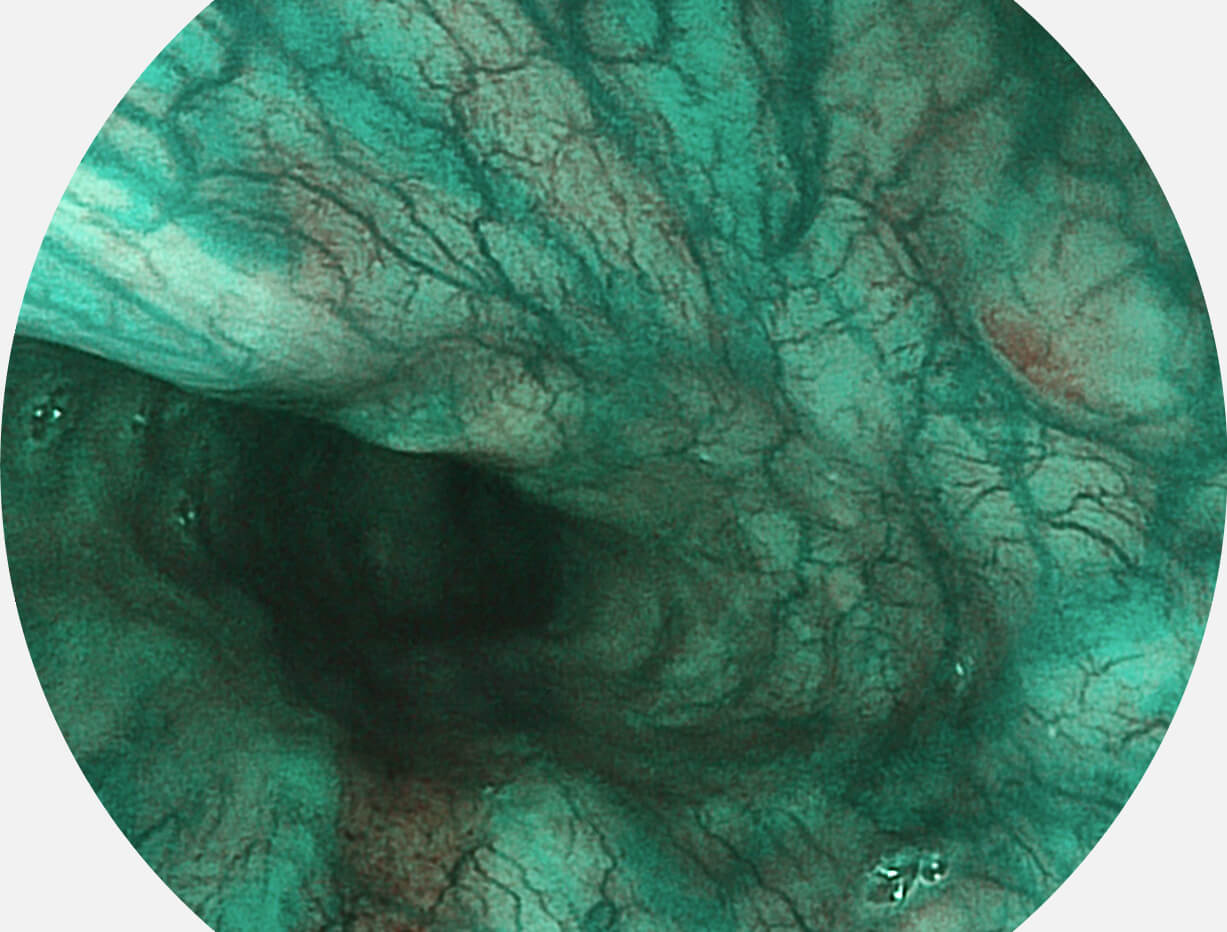

Versatile Intelligent Staining Technology, VIST

强调浅层黏膜结构的同时,保证照明亮度和提升浅层微血管与中层血管颜色对比度,病变边界更清晰。

采用光路合束技术,光谱自由度高,实现了更丰富的照明模式,染色模式SFI及VIST,从远景到近景,助力消化道早期疾病诊断。